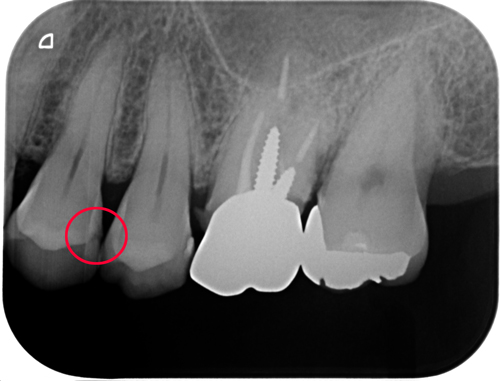

ホワイトニングを2クール。その後左上(画像では向かって右)をダイレクトボンディング。さらに右上の補綴物を交換しました。